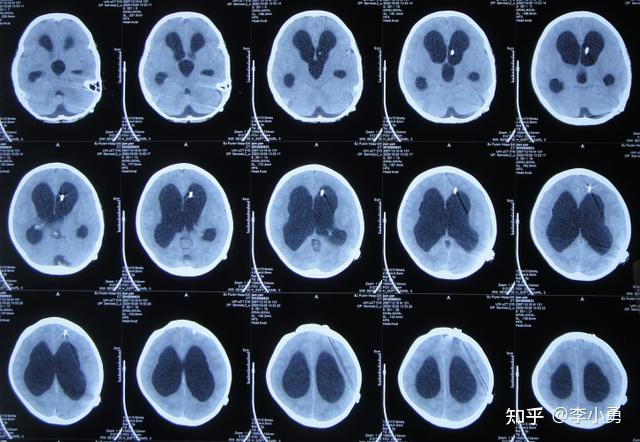

26岁已婚患者结核性脑膜炎继发脑积水9年2次分流术后堵管3年经李小勇

图片尺寸640x464